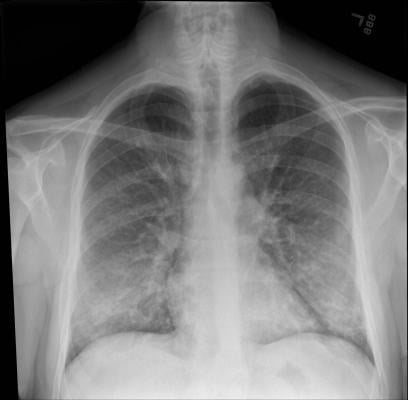

In the study, Intermountain Healthcare researchers identified 60 E-VALI patients at 13 different Intermountain hospitals or clinics in Utah from June 27, 2019, through October 4, 2019. The diagnosis was defined by a history of vaping or e-cigarette use within 90 days prior to symptoms, abnormalities shown in chest imaging, and no other cause for these findings (such as pneumonia).

In the first study to report follow-up findings for these patients, Intermountain clinicians performed a short follow-up exam after two weeks and found that, although most patients had improved significantly, many had residual abnormalities. Only 23 percent of the patients still needed supplementary oxygen, but most still showed some signs of lung abnormalities on their imaging and breathing tests.

These findings are helping physicians recognize what lung injuries associated with e-cigarettes or vaping look like — and helping them maintain a high degree of suspicion when they diagnose lung injuries in patients who've been vaping.